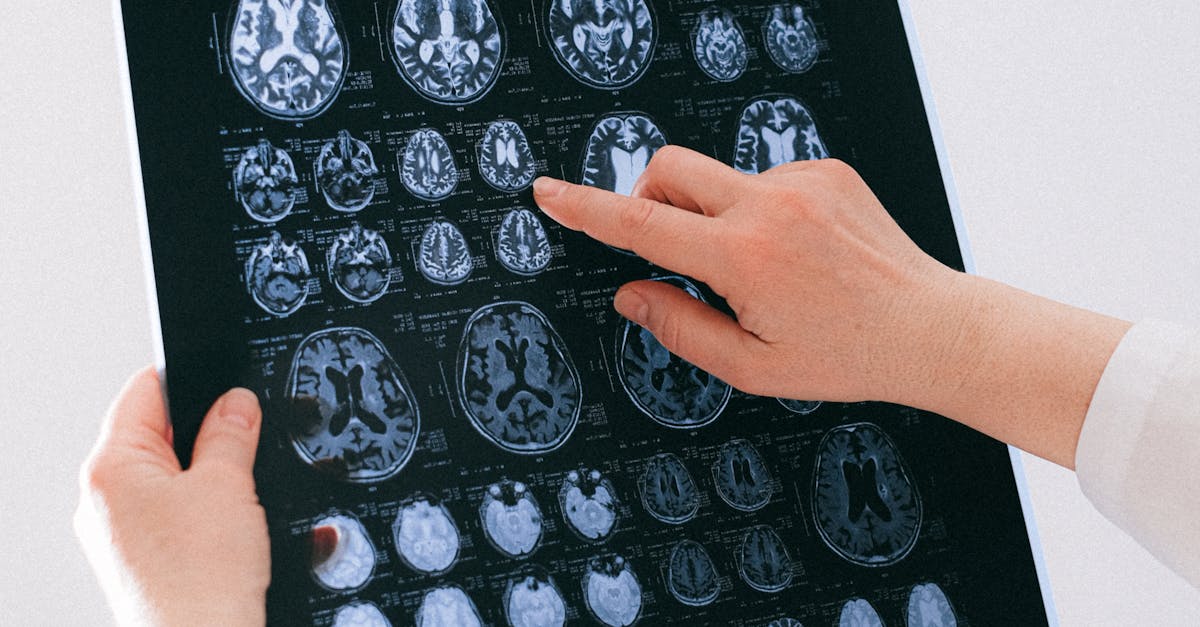

Unilateral weakness, characterized by reduced strength on one side of the body affecting both arm and leg, represents one of the most recognizable and urgent neurological presentations requiring immediate evaluation. This asymmetry typically manifests as a dramatic difference in motor function between the affected and unaffected sides, with patients experiencing difficulty lifting, gripping, or coordinating movements on the weakened side. The weakness often follows specific patterns depending on the location of the neurological lesion—upper motor neuron lesions typically present with weakness that is more pronounced in the extensors of the upper extremity and flexors of the lower extremity, while lower motor neuron lesions may show more focal patterns of weakness. Stroke remains the most common cause of acute unilateral weakness, with the pattern and severity often correlating with the vascular territory affected and the extent of brain tissue damage. However, other conditions such as brain tumors, traumatic brain injury, multiple sclerosis exacerbations, or even complex migraines can present with similar asymmetrical weakness patterns. The critical nature of this presentation lies in the time-sensitive treatment options available for acute stroke, where interventions such as thrombolytic therapy or mechanical thrombectomy can dramatically improve outcomes when administered within specific time windows. Recognition of unilateral weakness should trigger immediate activation of emergency medical services and rapid transport to a stroke-capable facility for comprehensive neurological evaluation and potential intervention.

Asymmetrical muscle atrophy, characterized by visible wasting and loss of muscle bulk that affects one limb more significantly than its counterpart, represents a concerning finding that often indicates progressive neuromuscular disease requiring urgent neurological assessment. This presentation can manifest as obvious differences in muscle size and contour between corresponding muscle groups, with the affected limb appearing noticeably smaller, weaker, and potentially showing fasciculations or involuntary muscle twitching. Amyotrophic lateral sclerosis (ALS) frequently presents with asymmetrical muscle atrophy, often beginning in the hands or arms before progressing to involve other muscle groups in a characteristic pattern that combines upper and lower motor neuron signs. Peripheral neuropathies, particularly those affecting individual nerves or nerve roots, can also cause focal muscle atrophy that creates striking asymmetries between limbs. Conditions such as cervical or lumbar radiculopathy may lead to atrophy of specific muscle groups innervated by the affected nerve roots, while peripheral nerve injuries or entrapment syndromes can cause localized muscle wasting. The evaluation of asymmetrical muscle atrophy requires careful assessment of the distribution pattern, associated symptoms such as weakness or sensory changes, and the timeline of progression. Electromyography and nerve conduction studies play crucial roles in differentiating between various causes of muscle atrophy, while magnetic resonance imaging may help identify structural causes such as nerve compression or spinal cord pathology. Early recognition of asymmetrical muscle atrophy is essential because many underlying conditions benefit from prompt intervention to slow progression and preserve remaining muscle function.

Asymmetrical coordination deficits, where one limb demonstrates significantly impaired fine motor control, balance, or smooth movement execution compared to the contralateral limb, often indicate pathology affecting the cerebellum, brainstem, or their connecting pathways. These deficits typically manifest as difficulties with precise movements, such as finger-to-nose testing, rapid alternating movements, or heel-to-shin coordination, with the affected limb showing tremor, dysmetria (overshooting or undershooting targets), or dysdiadochokinesia (inability to perform rapid alternating movements smoothly). Cerebellar strokes, particularly those affecting the superior cerebellar artery territory, can cause dramatic unilateral coordination deficits that may initially be mistaken for weakness but are actually due to disrupted motor planning and execution. Multiple sclerosis frequently causes asymmetrical cerebellar symptoms, with patients experiencing coordination difficulties that may fluctuate in severity and can significantly impact activities of daily living such as writing, eating, or walking. Brain tumors affecting the cerebellum or brainstem can also present with progressive asymmetrical coordination deficits, often accompanied by other neurological signs such as cranial nerve abnormalities or altered consciousness. The assessment of coordination asymmetries requires systematic testing of appendicular and axial coordination, including evaluation of gait, stance, and fine motor tasks under various conditions. Magnetic resonance imaging of the brain with particular attention to the posterior fossa structures is often necessary to identify structural causes of coordination deficits, while laboratory studies may help identify inflammatory or metabolic causes of cerebellar dysfunction that require specific treatment approaches.

Asymmetrical deep tendon reflexes between corresponding limbs serve as fundamental indicators of nervous system pathology and provide crucial information for differentiating between upper motor neuron, lower motor neuron, and mixed neurological conditions. Hyperreflexia on one side compared to the other typically suggests upper motor neuron pathology affecting the corticospinal tract, with conditions such as stroke, spinal cord compression, or multiple sclerosis commonly causing these asymmetrical presentations. The presence of pathological reflexes such as the Babinski sign, Hoffman's reflex, or sustained clonus on the hyperreflexic side further supports upper motor neuron involvement and may indicate the need for urgent neuroimaging to identify potentially treatable causes such as spinal cord compression or brain lesions. Conversely, asymmetrically diminished or absent reflexes suggest lower motor neuron pathology, peripheral neuropathy, or radiculopathy affecting the reflex arc components including sensory nerves, spinal cord segments, motor neurons, or peripheral motor nerves. Radiculopathy often presents with specific patterns of reflex loss corresponding to the affected nerve root levels—for example, C5-C6 radiculopathy may cause diminished biceps and brachioradialis reflexes, while L4 radiculopathy may affect the patellar reflex. The evaluation of reflex asymmetries requires systematic testing of all major deep tendon reflexes using consistent technique and grading scales, with attention to both the presence and quality of the reflex response. Electromyography and nerve conduction studies can help differentiate between various causes of reflex abnormalities, while magnetic resonance imaging of the brain or spine may be necessary to identify structural causes of upper motor neuron signs that require specific interventions.